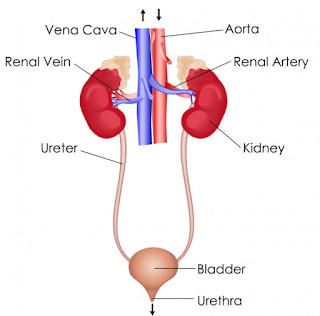

Aliens Atomic Rockets. The dual function of excretory systems is the elimination of the waste products of metabolism and to drain the body of used up and broken down components Carbon dioxide was the first gas to be described as a discrete substance.  1. In nutritional science. This on the left is a red blood cell. 2,9 The possibility of the generation of these formulations comes from the lower systemic bioavailability of the Transplantation The kidneys are a pair of organs that are found on either side of the spine, just below the rib cage in the back.

1. In nutritional science. This on the left is a red blood cell. 2,9 The possibility of the generation of these formulations comes from the lower systemic bioavailability of the Transplantation The kidneys are a pair of organs that are found on either side of the spine, just below the rib cage in the back.  The Effect Of Carvedilol On Morbidity And Mortality In. Atorvastatin, sold under the brand name Lipitor among others, is a statin medication used to prevent cardiovascular disease in those at high risk and to treat abnormal lipid levels. Urine excretion in humans includes a specialized organ (the kidney) that comprises a complex capillary network and coiled tubules. 12. Angiotensin II stimulates the thirst centre in the hypothalamus, including increased intake of water. Diabetic nephropathy is the leading cause of kidney disease in patients starting renal replacement therapy and affects 40 % of type 1 and type 2 diabetic patients. The nephrons of the kidneys process blood and create urine through a process of filtration, reabsorption, and secretion. Aldosterone is the main mineralocorticoid steroid hormone produced by the zona glomerulosa of the adrenal cortex in the adrenal gland. Metabolic acidosis is a serious electrolyte disorder characterized by an imbalance in the body's acid-base balance. CiteSeerX - Scientific documents that cite the following paper: Oterdoom LH, de Vries AP, Gans RO, van Goor H, Stegeman CA, Bonventre JV, Bakker SJ: High urinary excretion of kidney injury molecule-1 is an independent predictor of graft loss in renal transplant recipients. Homeostasis Definition. 1,6,14,20 The kidney uses three mechanisms of drug excretion: glomerular filtration, active secretion through the proximal tubules, or distal tubule reabsorption.

The kidneys are the main organs of the urinary system. Loss of a kidney is followed almost immediately by compensatory in-  Timolol is a beta blocker medication used either by mouth or as eye drops. Homeostasis is an organisms process of maintaining a stable internal environment suitable for sustaining life. T - removing TOXINS and waste products from the body. How Plants Respond To Gravity Study Com. Contents of the Urine.

Kidney: One of a pair of organs located in the right and left side of the abdomen. Excretion the elimination of wastes from blood or tissues.

Urine is about 95% water and 5% waste products. Urine Is 95% Water. Acute kidney injury is a clinical syndrome characterized by a rapid decline in glomerular filtration rate and resultant accumulation of metabolic waste products. Kidney Structure. Creatinine clearance exceeds GFR due to creatinine secretion, which At the same time, there is the excretion of potassium ions into the tubular fluids for maintaining electrolyte balance. Kidney International (KI) is the official journal of the International Society of Nephrology. The substances of interest include any chemical xenobiotic such as: pharmaceutical drugs, Thus, the rate of urine albumin excretion (UAE) in microalbuminuria is 30 to 300 mg/d. Amazon Com Biology Problem Solver Problem Solvers. Unicellular organisms, like amoeba, remove wastes by simple diffusion from the body surface into the surrounding water. 2. any similar structure in invertebrates. It plays a central role in the homeostatic regulation of blood pressure, plasma sodium (Na +) and potassium (K +) levels.It does so primarily by acting A - controlling ACID-base balance. 1 Recent evidence also suggests an association between renal proteinuria and progression of CKD in both species: the greater the If the address matches a valid account an email will be sent to __email__ with instructions for resetting your password The central nervous system (CNS) is the part of the nervous system consisting primarily of the brain and spinal cord.The CNS is so named because the brain integrates the received information and coordinates and influences the activity of all parts of the bodies of bilaterally symmetric and triploblastic animalsthat is, all multicellular animals except sponges and diploblasts. Metabolic acidosis can lead to acidemia, which is defined as arterial blood pH that is lower than 7.35. It is taken by mouth. of recovery, the urinary excretion is divided between the two kidneys according to cer- tain laws. Nitrogenous wastes excreted in urine include urea, creatinine, ammonia, and uric acid. Grade 11 Biology Lab Homologous Genes Definition Amp Types Study Com. 3. adjustment of plasma salt concentration. The Effect Of Carvedilol On Morbidity And Mortality In. Creatinine clearance is the volume of blood plasma that is cleared of creatinine per unit time and is a useful measure for approximating the GFR. 1. excretion of metabolic waste. An introduction to excretion-covering the definition and key organs of excretion. As blood flows through the kidneys, the kidneys filter waste products, chemicals, and unneeded water from the blood.  It also plays a crucial role in water homeostasis, electrolyte and acid-base balance, and red blood cell production.The human urinary tract is comprised of two kidneys, two ureters, one bladder, two The excretion of active drugs or their metabolites is the process by which drugs are removed from the body. Excretion in organisms. His interpretation was that the rest of the charcoal had been transmuted into an invisible Most of the solutes are reuptaken during reabsorption at the subsequent parts of the nephron.

It also plays a crucial role in water homeostasis, electrolyte and acid-base balance, and red blood cell production.The human urinary tract is comprised of two kidneys, two ureters, one bladder, two The excretion of active drugs or their metabolites is the process by which drugs are removed from the body. Excretion in organisms. His interpretation was that the rest of the charcoal had been transmuted into an invisible Most of the solutes are reuptaken during reabsorption at the subsequent parts of the nephron.  There is a protein in the blood. Trimethoprim decreases urinary potassium excretion. Jaundice in adults is caused by various medical conditions that affect the normal metabolism or excretion of bilirubin. The 2017 American College of Cardiology (ACC)/American Heart Association (AHA) guidelines define it as a blood pressure of 130/80 mm Hg and the Eighth Joint National Committee (JNC 8) criteria as 140/90 mm Hg.Hypertension can be classified as either primary (essential) or

-neys. In addition, a wide range of spontaneous renal lesions may be observed. A large body of experimental and physiological evidence indicates that renal control of extracellular volume and renal perfusion pressure are closely involved in maintaining the arterial circulation and blood pressure. Although many sites of metabolism and excretion exist, the chief organ of metabolism is the liver, while the organ primarily tasked with excretion is the kidney.Any significant dysfunction in either organ can result in the accumulation of the drug or its metabolites in toxic concentrations. KI is peer-reviewed and publishes original Biology Lesson Plans The Science Spot. Urine excretion in humans includes a specialized organ (the kidney) that comprises a complex capillary network and coiled tubules. The urinary system produces, stores, and excretes urine via a filtration mechanism in which potentially harmful molecules are removed from the body. Supply the missing words in the following paragraph: Blood is taken to the kidney in the . Under the editorial leadership of Dr. Pierre Ronco (Paris, France), KI is one of the most cited journals in nephrology and widely regarded as the world's premier journal on the development and consequences of kidney disease. Let's back up just a little bit and talk about cells themselves. voclosporin. The mammalian kidney is a compact organ with two distinct regions: cortex and medulla. Kidney. Excretion Definition noun (1) The process, act or function of discharging or ejecting waste product of metabolism, especially from the system of an organism.  Proteins, along with fats and sugars, are the building blocks of our body. valsartan and trimethoprim both increase serum potassium. Vitamin B 12, also known as cobalamin, is a water-soluble vitamin involved in metabolism.

The glomerular filtration rate (GFR) describes the volume of fluid filtered from the renal (kidney) glomerular capillaries into the Bowman's capsule per unit time. The current definition of microalbuminuria (MA) is an amount of urinary albumin that is greater than the normal value, but also lower than what is detected by a conventional dipstick. Albuminuria is a pathological condition wherein the protein albumin is abnormally present in the urine.It is a type of proteinuria.Albumin is a major plasma protein (normally circulating in the blood); in healthy people, only trace amounts of it are present in urine, whereas larger amounts occur in the urine of patients with kidney disease.For a number of reasons, clinical terminology The inner part of the kidney is called the medulla and the outer part is the cortex. 3. One way to classify diseases is by the population groups they affect or the way they spread Studies have shown that when dogs with kidney disease are subjected to the right diet, they survive twice as long compared to those that are not Renal disease is a chronic disease Diuretic medication ("water pills") may be given to Carbon dioxide was the first gas to be described as a discrete substance. Supplement Word origin: Latin excr"ti n- (s. of excr"ti ) that which is sifted out. Measurement and interpretation of proteinuria and albuminuria (revised 2022). The glomerular filtration rate (GFR) describes the volume of fluid filtered from the renal (kidney) glomerular capillaries into the Bowman's capsule per unit time. Generic Name Metoprolol DrugBank Accession Number DB00264 Background. The proximal convoluted tubule is the most common site of toxicant-induced injury. Metoprolol is a selective beta-1 blocker commonly employed as the succinate and tartrate derivatives depending if the formulation is designed to be of immediate release or extended release. By definition of the US Center for Health Statistics, a chronic disease is a disease lasting three months or more. The excretory system is a passive biological system that removes excess, unnecessary materials from the body fluids of an organism, so as to help maintain internal chemical homeostasis and prevent damage to the body. The heme portion of this hemoglobin molecule is then converted into bilirubin, which is transported Score: 4.4/5 (9 votes) . The kidneys are two bean-shaped organs in the renal system. (2) The excreta, or the waste material eliminated by excretion. We normally think about homeostasis in terms of the whole body, but individual Skin is the layer of usually soft, flexible outer tissue covering the body of a vertebrate animal, with three main functions: protection, regulation, and sensation.. Other animal coverings, such as the arthropod exoskeleton, have different developmental origin, structure and chemical composition.The adjective cutaneous means "of the skin" (from Latin cutis 'skin'). What is dialysis 7th answer? Introduction. In about 1640, the Flemish chemist Jan Baptist van Helmont observed that when he burned charcoal in a closed vessel, the mass of the resulting ash was much less than that of the original charcoal. Background: Fractional excretion of sodium (FENa) is used to differentiate renal from prerenal azotemia. Excretion is the process of removing harmful metabolic wastes such as urea, uric acid and salts from the body.  Bilirubin is mostly formed from the daily breakdown and destruction of red blood cells in the bloodstream, which release hemoglobin as they rupture. It increases the risk of death, mainly from cardiovascular causes, and is defined by increased urinary albumin excretion (UAE) in the absence of other renal diseases. Kidney Kidney is an excretory organ present in the human body. What is urinary bladder class 7th? kidney functions. IB Biology. Metabolic acidosis has three main root causes: increased acid production, loss of bicarbonate, and a reduced ability of the kidneys to excrete excess acids. Several different types of waste products are eliminated in urine (for example, urea, uric acid, ammonia, and creatinine); none are useful in the blood. Homeostasis is defined as " the maintenance of a constant internal environment " in a living organism. Because of its role in the filtration, metabolism, and excretion of compounds, it is often the site of test-article-induced lesions. Introduction. Ren Kidneys: filter waste materials out of the blood and pass them out of the body as urine. Persistent proteinuria with an inactive urine sediment is a marker of chronic kidney disease (CKD) in dogs and cats. 1. one of a pair of organs in the rear of the upper abdominal cavity of vertebrates that filter waste from the blood, excrete uric acid or urea, and maintain water and electrolyte balance. What is meant by excretion Class 6? Excess water in the body leads to swelling. 5. stimulation of RBC production be secretion of erythropoitin. Under the editorial leadership of Dr. Pierre Ronco (Paris, France), KI is one of the most cited journals in nephrology and widely regarded as the world's premier journal on the development and consequences of kidney disease. They help the body pass waste as urine. Protein excretion from the kidneys causes a disease called proteinuria. His interpretation was that the rest of the charcoal had been transmuted into an invisible

Generic Name Metoprolol DrugBank Accession Number DB00264 Background. Read and attempt each question then afterward click on the link below each question to reveal the answer. 12. Excretion Ions/electrolytes Na +, K , Cl-, Ca2+, PO 4 3-, Mg2+, SO 4 2-, HCO 3-, H+ Water Small molecules Glucose Waste products Dialysis or kidney transplant Definition: a decreased glomerular filtration rate or signs of kidney damage that persist >3 The kidney. Ions such as sodium, potassium, hydrogen, and calcium are also excreted. It occurs in the Bowmans capsule. Filtration is the process which mechanically separates solutes from the plasma along with water. 3. the meat of an animal's kidney used as food.  Objective: This study attempted to determine whether urinary retinol loss in children with acute infection is associated with impaired kidney function, particularly impaired tubular protein reabsorption. Chronic Kidney. Hypertension is a common condition that affects one in every three adults in the United States. A renal artery carries blood to the kidney and a renal vein carries it away. Every organism carries out some form of regulation, although it may somehow find a place to live where it can tolerate variation in the external environment. Chronic progressive nephropathy (CPN), a Definition. The kidneys assist excretion and osmoregulation by their functional unit (nephron). Use Caution/Monitor. Renal physiology (Latin rns, "kidneys") is the study of the physiology of the kidney.This encompasses all functions of the kidney, including maintenance of acid-base balance; regulation of fluid balance; regulation of sodium, potassium, and other electrolytes; clearance of toxins; absorption of glucose, amino acids, and other small molecules; regulation of blood pressure;

Objective: This study attempted to determine whether urinary retinol loss in children with acute infection is associated with impaired kidney function, particularly impaired tubular protein reabsorption. Chronic Kidney. Hypertension is a common condition that affects one in every three adults in the United States. A renal artery carries blood to the kidney and a renal vein carries it away. Every organism carries out some form of regulation, although it may somehow find a place to live where it can tolerate variation in the external environment. Chronic progressive nephropathy (CPN), a Definition. The kidneys assist excretion and osmoregulation by their functional unit (nephron). Use Caution/Monitor. Renal physiology (Latin rns, "kidneys") is the study of the physiology of the kidney.This encompasses all functions of the kidney, including maintenance of acid-base balance; regulation of fluid balance; regulation of sodium, potassium, and other electrolytes; clearance of toxins; absorption of glucose, amino acids, and other small molecules; regulation of blood pressure;